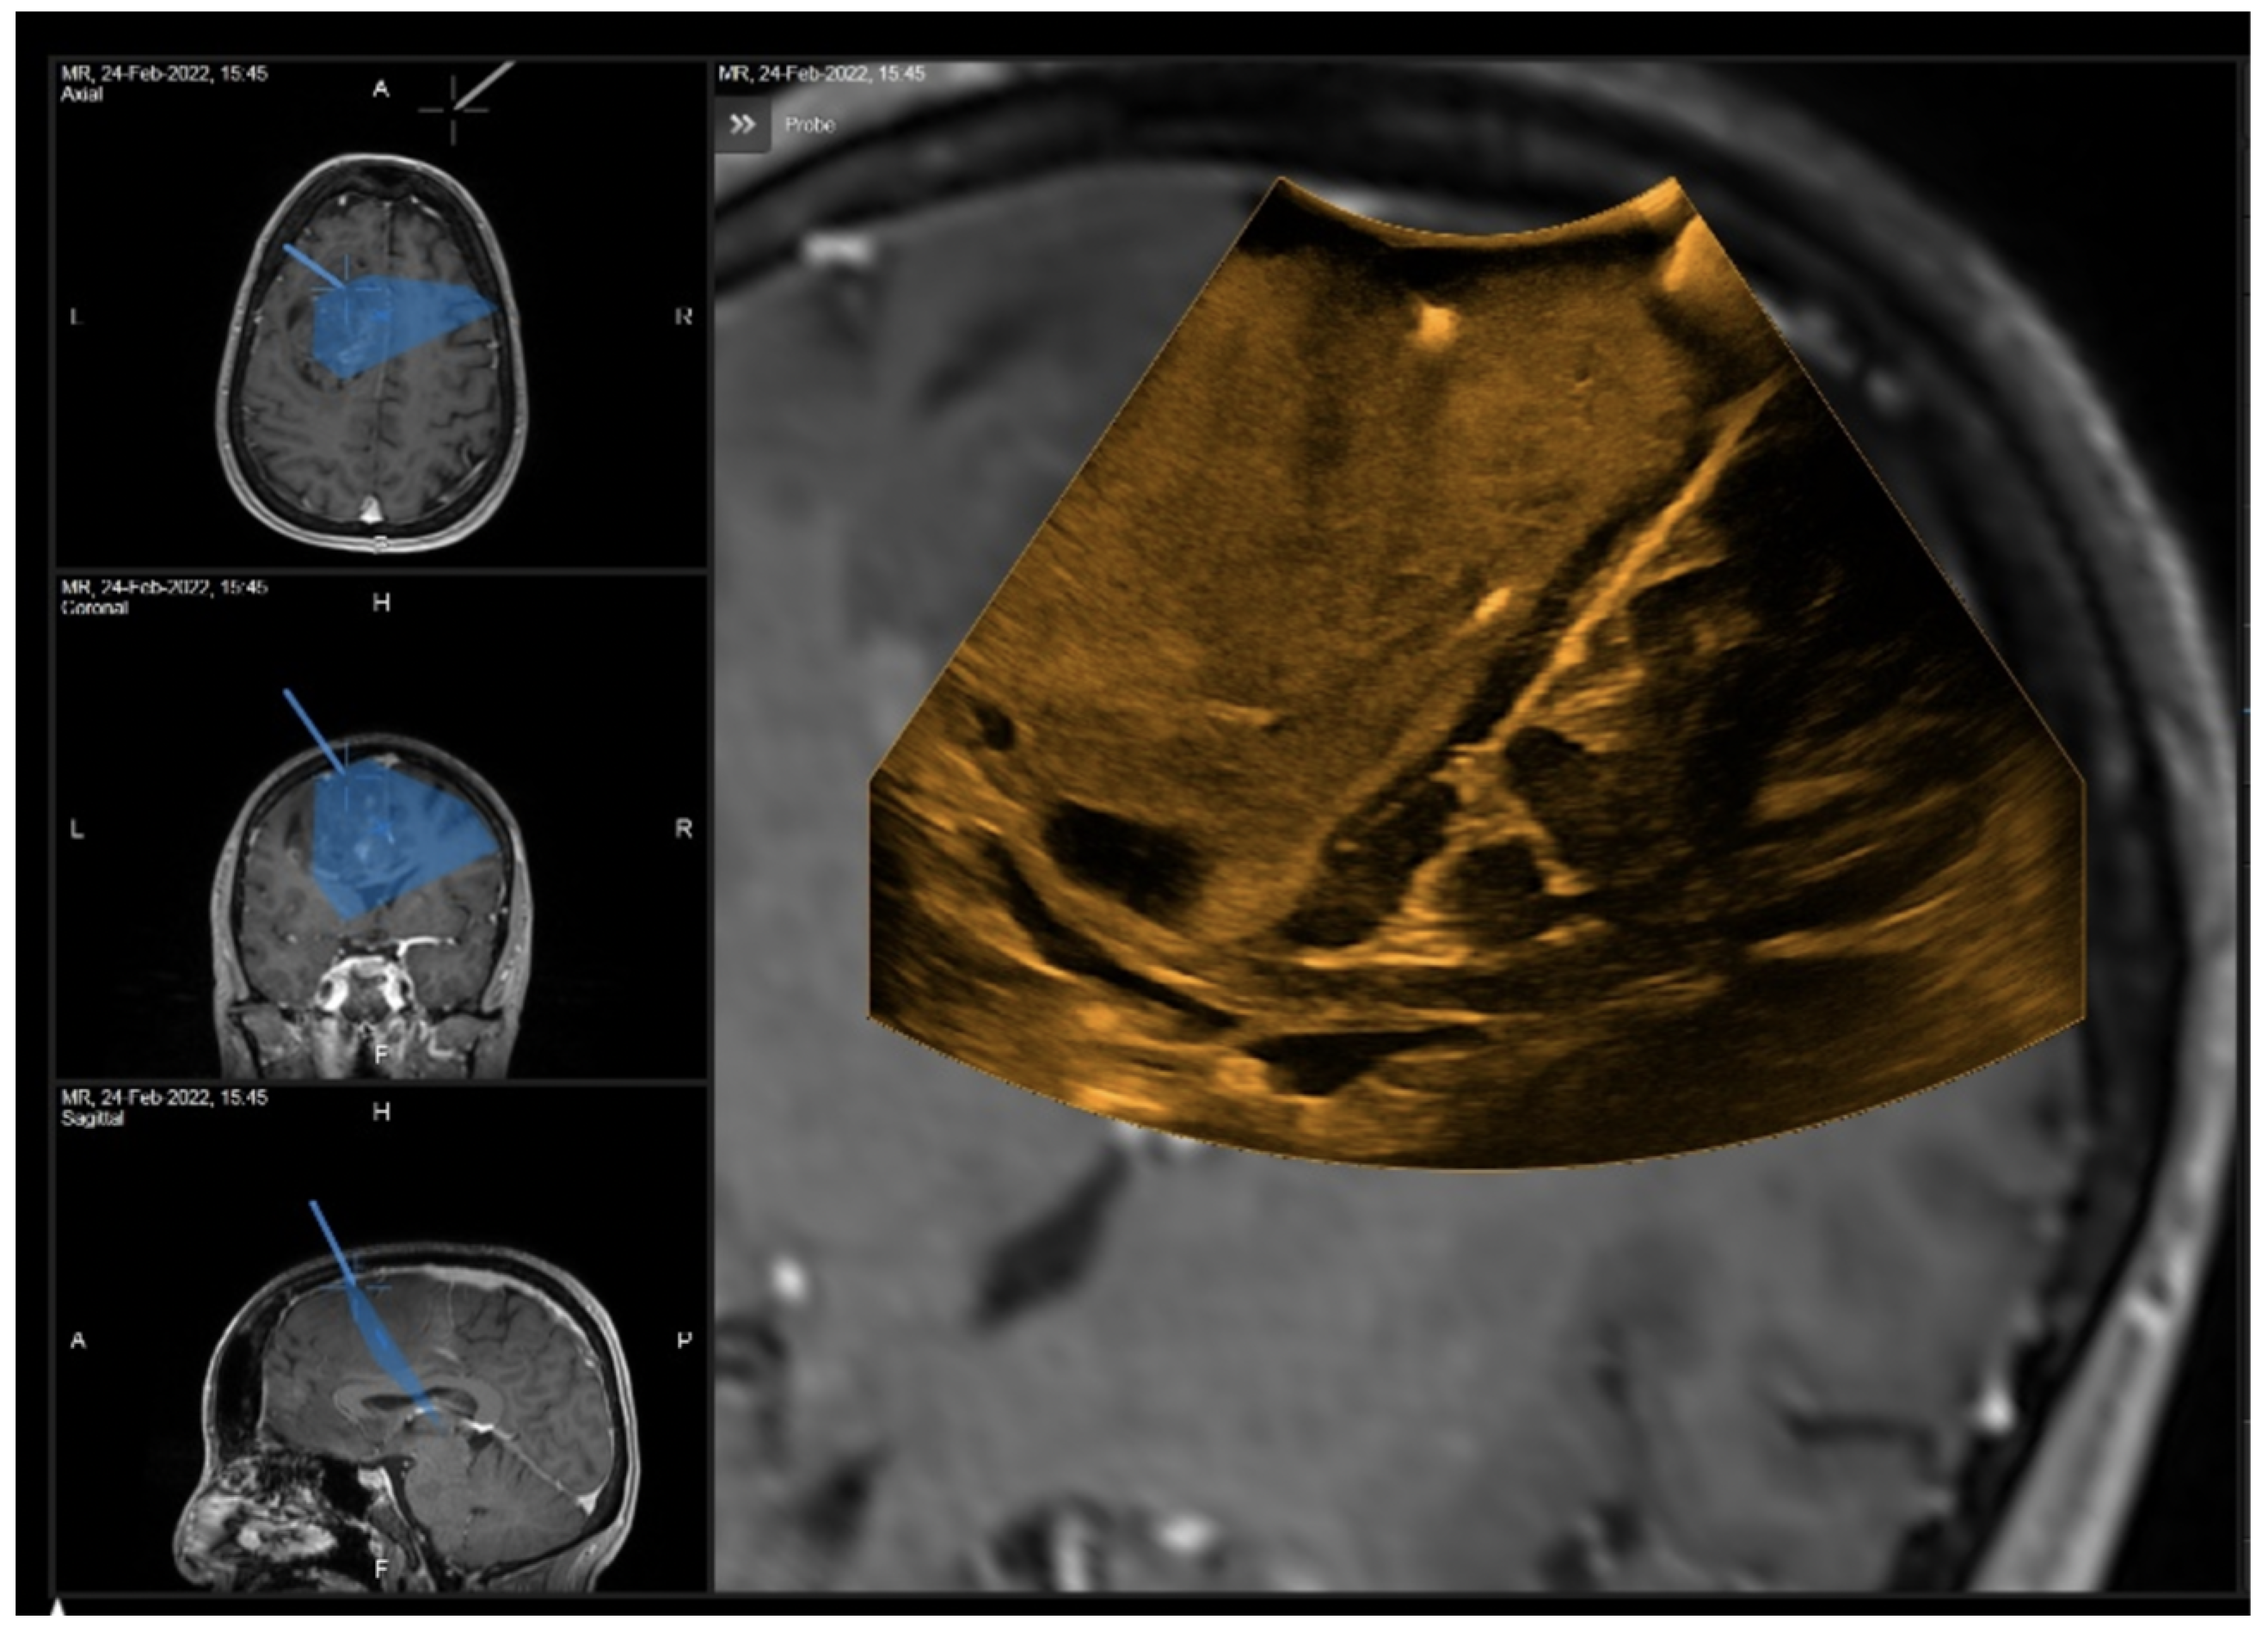

3.1.1. Case 1

3.1.2. Case 2